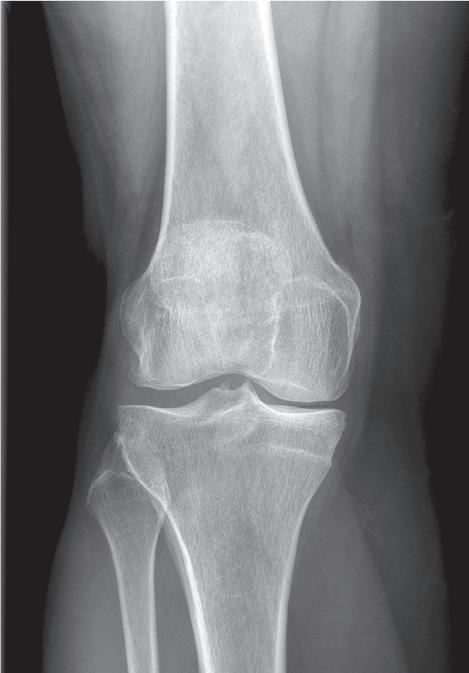

Základem diagnózy je klinické vyšetření doplněné o rentgenový snímek obvykle ve dvou projekcích

Obr. 19.2: Varózní deformita pravého kolenního kloubu (levé koleno již po korekci osy v rámci implantace náhrady kolenního kloubu) – (a) a rentgenový nález úhlové deformity s nálezem pokročilých artrotických změn (b)

(předozadní a bočná). Na rentgenovém snímku se gonartróza zpočátku projevuje přihrocením interkondylické eminence a subchondrální sklerózou v místě přetížení, později zúžením, případně až zánikem kloubní štěrbiny, vznikem osteofytů, pseudocyst a případnou úhlovou deformitou. Dle nálezu rovněž klasifikujeme stupeň gonartrózy podle Kellgrena-Lawrence (viz kap. 17, obr. 19.4), což má praktický význam v indikaci farmakoterapie i balneoterapie.